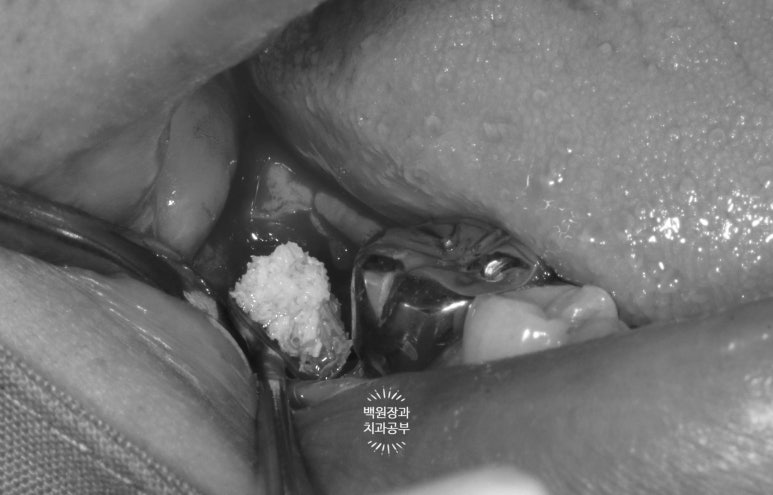

그래도 아쉬우니.. 충치라고 생각되는 부위를 제거해봅니다.

머리가 부러진 오른쪽 아래 어금니...

충치라고 생각되는 부위를 조심조심 제거해보았습니다.

보시면 안에 분홍색으로 동그랗게 보이시는게 있죠?? 옛날에 신경치료 때 사용했던 재료에요!

GP cone 입니다.

그 정도로 제거했는데도 여전히 까만색의 치아만 남아있네요...

이 치아는 뿌리 내부까지 썩었다고 판단되어 뽑기로 결정하였습니다.